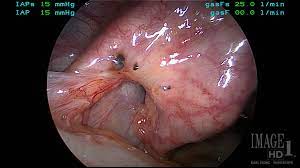

A case surgery for bladder endometriosis: Treatment of endometriosis after laparoscopic surgery: Endometriosis is defined as the presence of normal endometrial mucosa (glands and stroma) abnormally implanted in locations other than the uterine cavity (see the image below). Endometriosis is a full body condition in which cells similar to those in the endometrium, the layer of tissue that normally covers the inside of the uterus, grow outside the uterus. A pilot systematic review of the effects of aromatase inhibitors on pain associated with endometriosis.

Endometriosis is defined as the presence of normal endometrial mucosa (glands and stroma) abnormally implanted in locations other than the uterine cavity (see the image below). Treatment of endometriosis after laparoscopic surgery: Treatment of endometriosis and chronic pelvic pain with letrozole and norethindrone acetate: Endometriosis is the abnormal growth of endometrial cells outside the uterus. Endometriosis can be a challenging condition to manage. Endometriosis is more common in women who are having fertility issues, but it does not necessarily cause infertility. A randomized trial with an oxidized regenerated cellulose. Impact of endometriosis on quality of life and work productivity: